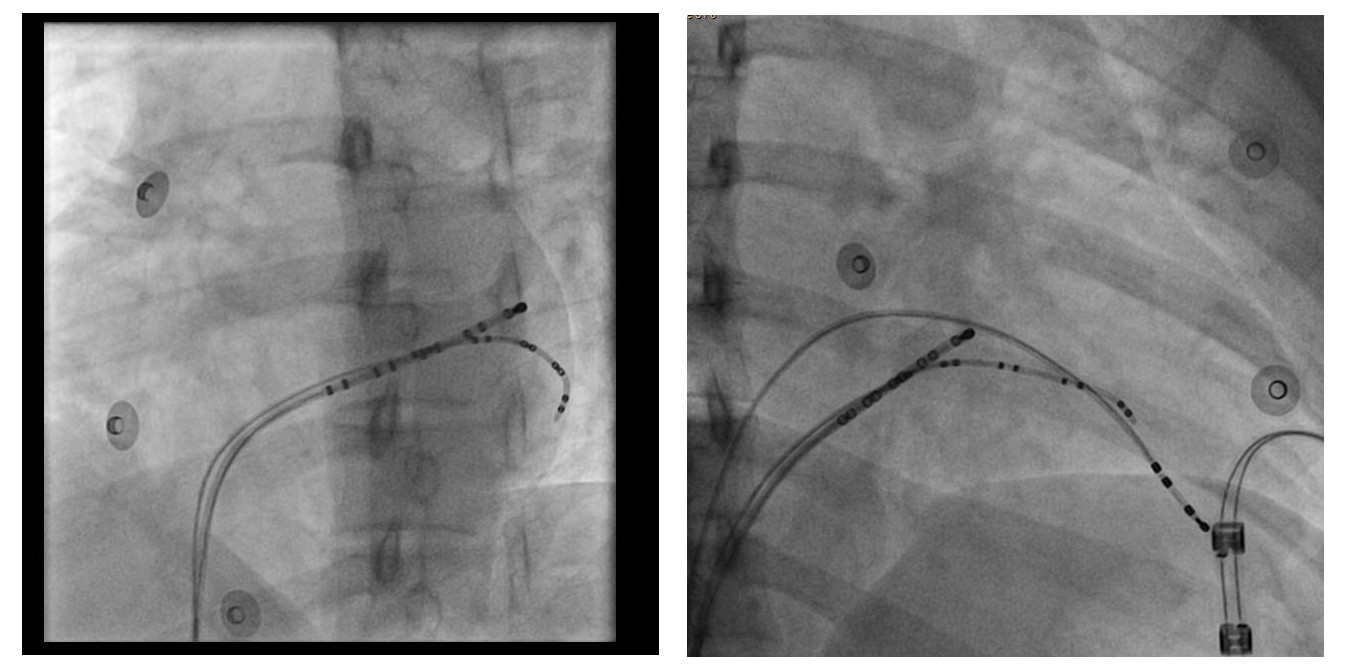

Right free wall

Sheath

sheath_rfwap.jpg

Under valve approach

under_valve_approach.png